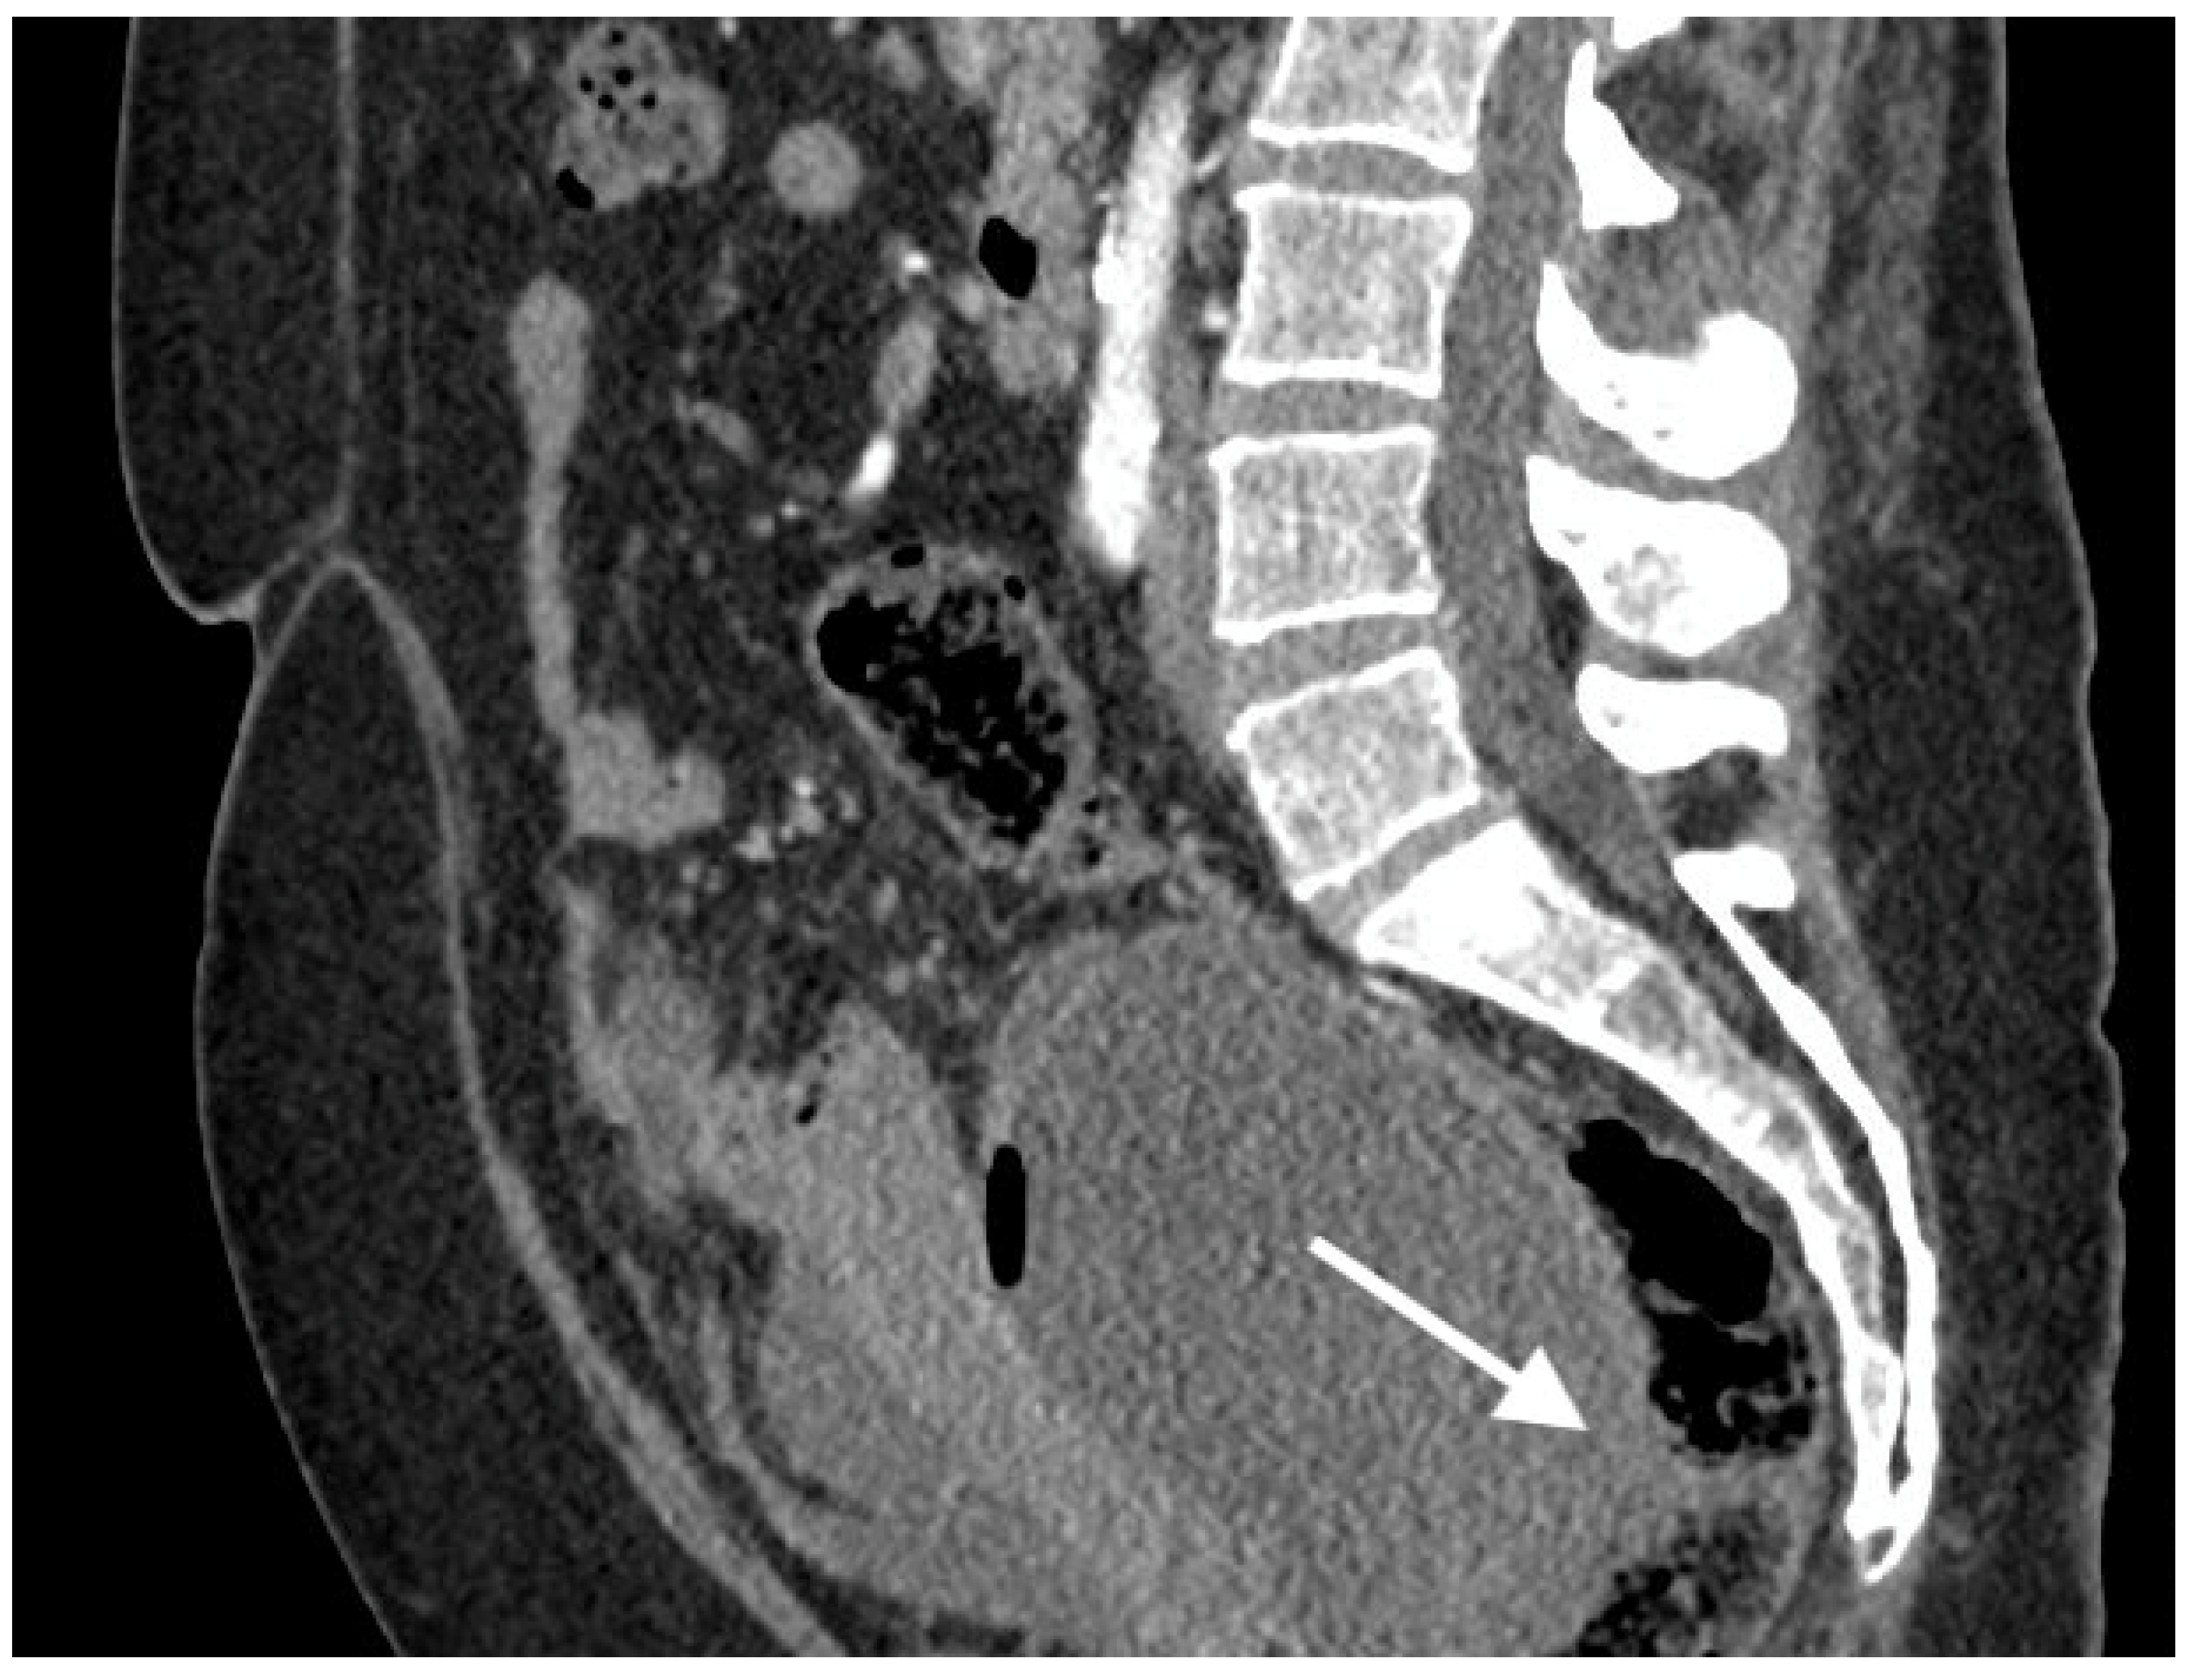

Figure 3.

Images of a 57-year-old patient with high-grade serous ovarian cancer recurrence. Computed tomography shows large cystic-solid pelvic tumor with fluid/gas level and adjacent rectum as indirect sign of fistula.

The median diameter of the relapsed tumor was 89 mm (range 36–130 mm). In all cases, fistulas formed between the tumor and large bowel. In three cases, fistulas formed between the rectum, including two between the sigmoid colon, one sigmoid and descending colon, one between the cecum and ascending colon, and one between the sigmoid colon and left ureter. On CT, in all cases, the fistulas were not directly visible, with only indirect signs of the fistula observed, such as infiltration of the intestine by the tumor, which we observed as vanishing of the fatty tissue between the tumor and the description of the intestinal wall, disruption of the intestinal wall, or the presence of gas in the tumor. In five patients, we observed thickening of the intestinal wall associated with a fistula (Figure 1, Figure 2 and Figure 3).

On computed tomography, we observed only indirect imaging signs of fistulas, such as infiltration of the intestine by the tumor, which we observed as vanishing of the fatty tissue between the tumor and the intestine, disruption of the intestinal wall, and gas in the tumor. Computed tomography’s limitation is evident when evaluating local tumor spread due to its lower soft tissue resolution. In other studies, CT was very useful for diagnosis, revealing indirect signs of fistulas, such as obvious thickening of the tumor wall and an air-fluid level within the tumor, suggesting that the ovarian tumor might have communication with the digestive tract; however, they also did not observe fistulas directly [11].